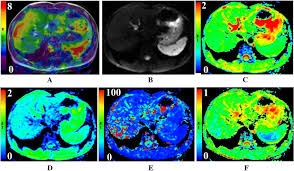

Treatment Induced Viral Cure Of Hepatitis C Virus Infected Patients Involves A Dynamic Interplay Among Three Important Molecular Players In Lipid Homeostasis Circulating Microrna Mir 24 Mir 223 And Proprotein Convertase Subtilisin Kexin Type 9

Treatment Induced Viral Cure Of Hepatitis C Virus Infected Patients Involves A Dynamic Interplay Among Three Important Molecular Players In Lipid Homeostasis Circulating Microrna Mir 24 Mir 223 And Proprotein Convertase Subtilisin Kexin Type 9 from els-jbs-prod-cdn.jbs.elsevierhealth.com